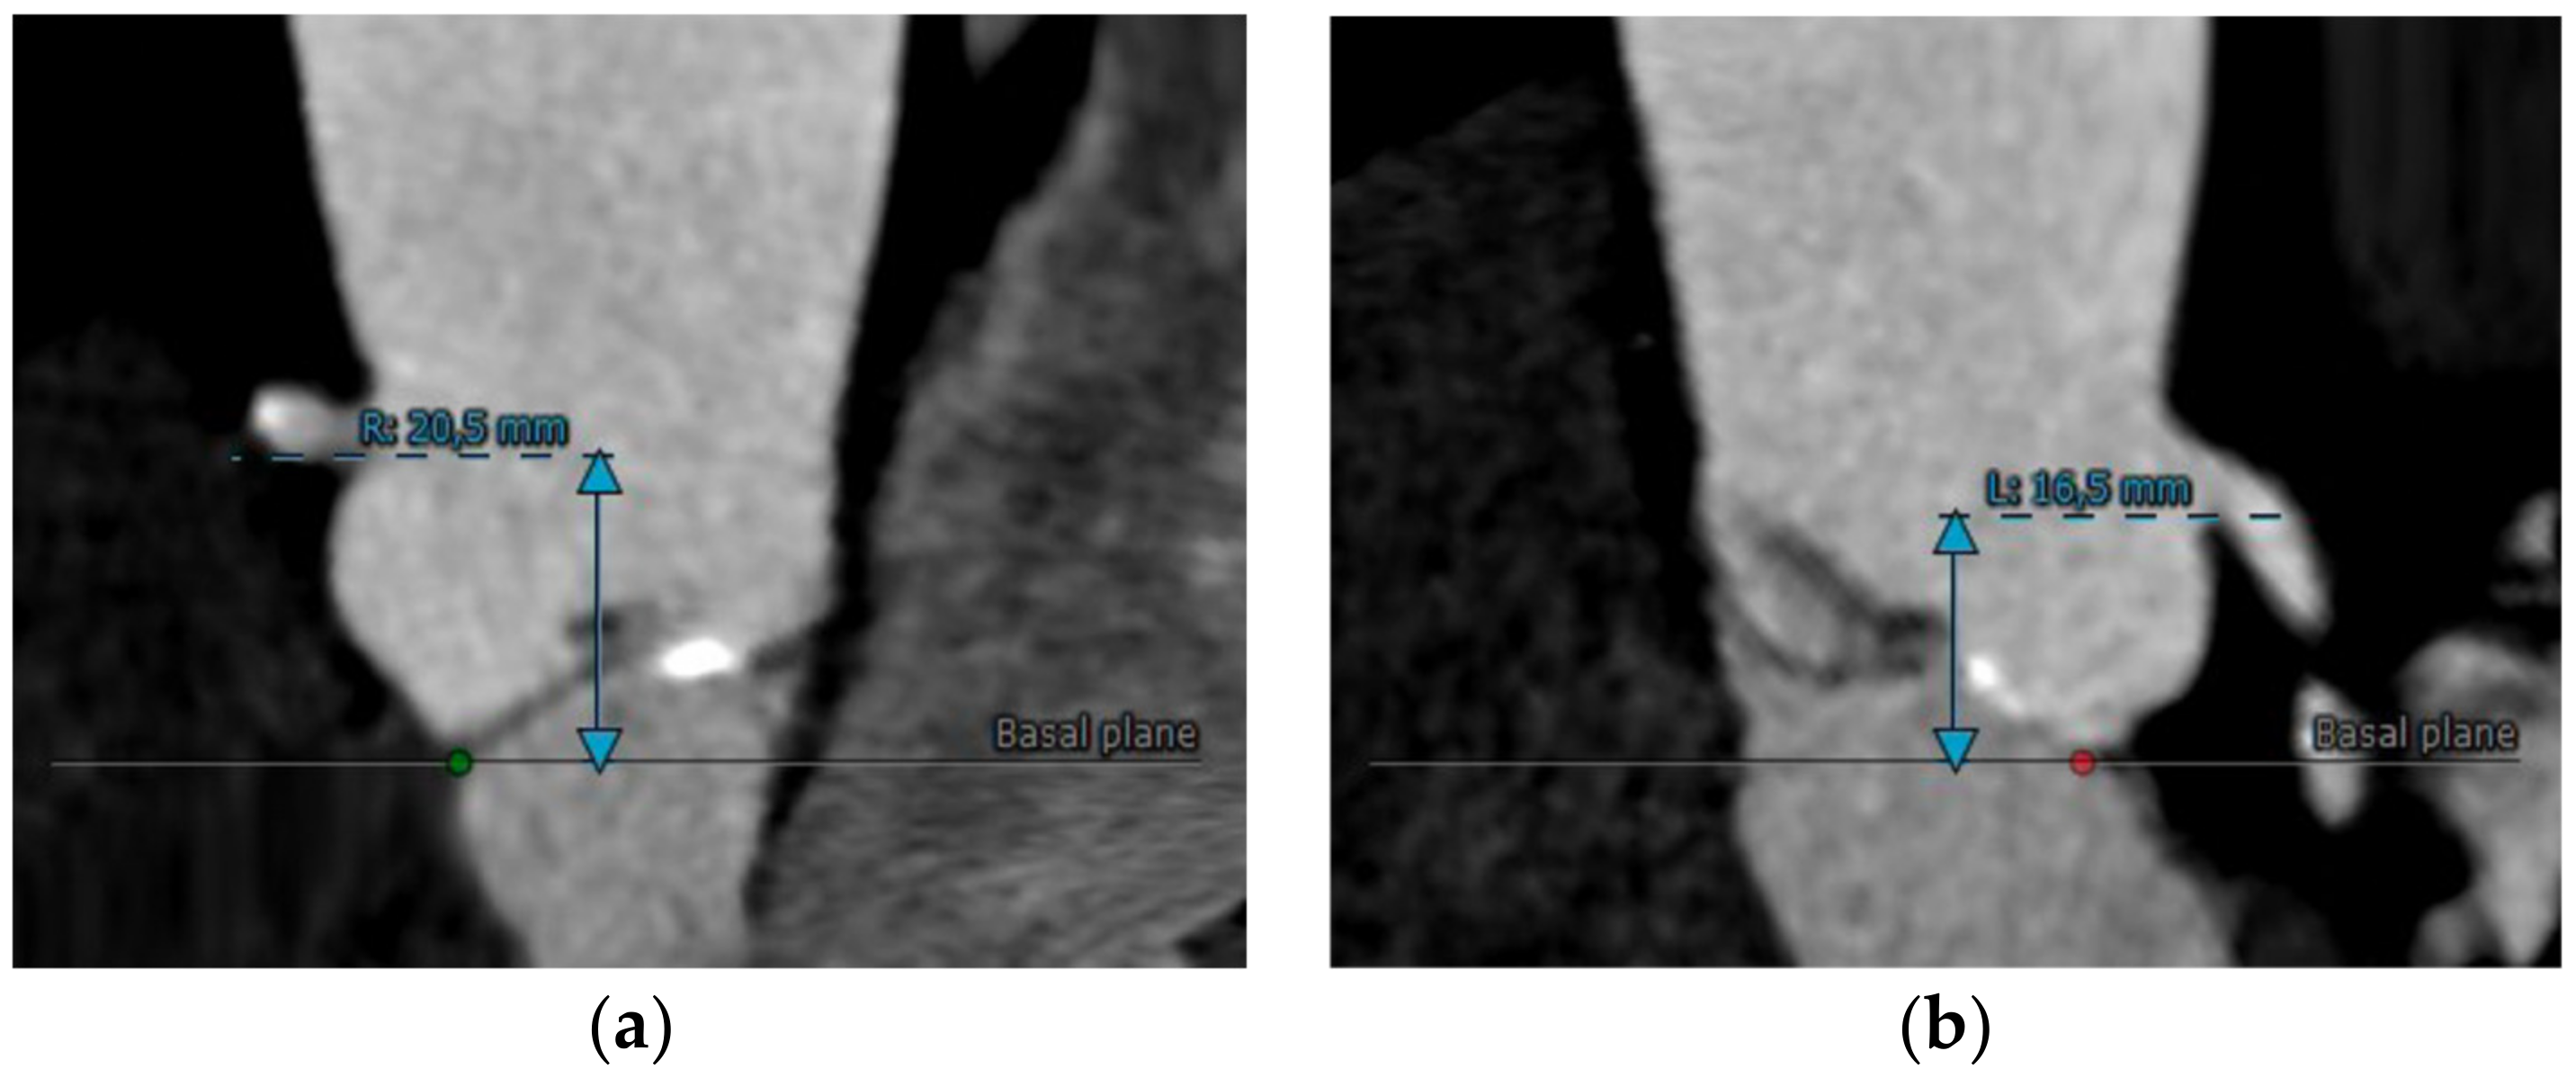

MDCT is crucial to identify the distance from the annulus/leaflet hinge point to the left main and right coronary ostia and the length of the corresponding coronary cusp (Figure 6a,b). Multiplanar, three-dimensional techniques allow better visualization and assessment of these complex structures and their relationships. For this reason, CT represents the preprocedural imaging gold standard for the evaluation of the risk of coronary occlusion. Even if there is no threshold value contraindicating the procedure, an increased risk of coronary occlusion was reported in patients with a coronary ostial height from the annulus < 12 mm and a sinus of Valsalva mean diameter < 30 mm. To ensure reproducibility, the height of the coronary ostia perpendicular to the plane of the annulus should be measured with an electronic caliper from the plane of the ring to the bottom of the ostium. No recommendations exist as to whether these measurements should be performed in systole or diastole [24].

Figure 6.

(a) Right and (b) left coronary ostia height assessment by CT images.

Ribeiro et al. found that coronary occlusion most commonly affects the left coronary (88.6 per cent) and occurs more commonly in women and following balloon expandable TAVI. In a systematic review, several parameters were found to be possible predictors of procedural complications: a low-lying coronary ostium < 10 to 12 mm from the basal leaflet insertion to the coronary ostium as measured by MDCT, mean sinus of Valsalva diameter of <30 mm, and sinus of Valsalva diameter/annular diameter ratio of <1.25. Furthermore, according to this analysis, women appear to be more subjected to coronary occlusion because of smaller aortic root dimensions and lower coronary ostial height [52]. Probably, significantly oversized THV or aortic root dissection, the displacement of native bulky aortic leaflets, impingement of the coronary ostia by the THV support structure, the embolization of calcium, thrombus, etc., are the mechanisms underlying coronary obstruction.